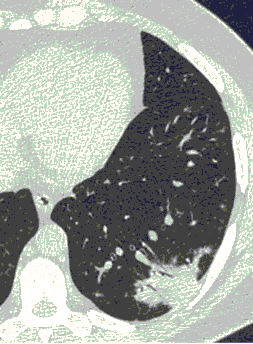

КТ имеет высокую чувствительность в выявлении изменений в легких, характерных для COVID-19. Применение КТ целесообразно для первичной оценки состояния ОГК у пациентов с тяжелыми прогрессирующими формами заболевания, а также для дифференциальной диагностики выявленных изменений и оценки динамики процесса. КТ позволяет выявить характерные изменения в легких у пациентов с COVID-19 еще до появления положительных лабораторных тестов на инфекцию с помощью МАНК. В то же время, КТ выявляет изменения легких у значительного числа пациентов с бессимптомной и легкой формами заболевания, которым не требуется госпитализация. Результаты КТ в этих случаях не влияют на тактику лечения и прогноз заболевания при наличии лабораторного подтверждения COVID-19. Поэтому массовое применение КТ для скрининга асимптомных и легких форм болезни не рекомендуется. При первичном обращении пациента с подозрением на COVID-19 рекомендуется назначать КТ только при наличии клинических и инструментальных признаков дыхательной недостаточности (SpO2 < 95%, ЧДД > 22).

Методы лучевой диагностики применяют для выявления COVID-19 пневмоний, их осложнений, дифференциальной диагностики с другими заболеваниями легких, а также для определения степени выраженности и динамики изменений, оценки эффективности проводимой терапии.

К методам лучевой диагностики патологии ОГК пациентов с предполагаемой/установленной COVID-19 пневмонией относят:

- Компьютерную томографию легких (КТ),